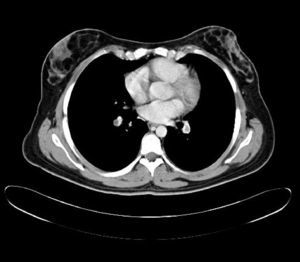

Durante el estudio le fue realizado una TAC que encontró tromboembolismo pulmonar bilateral sin repercusión clínica y trombosis venosa profunda de vena ilíaca izquierda, con síndrome de May-Thurner, como hallazgos casuales. El estudio de trombofilia familiar fue negativo. Se inició a continuación tratamiento anticoagulante. Recibió el alta con pauta de acenocumarol, de prednisona y levofloxacino, con mejoría clínica paulatina en las siguientes semanas (figs. 1 y 2).

Durante el estudio de la agranulocitosis de esta paciente se realizó una TAC, con el hallazgo casual de trombosis pulmonar bilateral con trombosis venosa profunda de la ilíaca común izquierda con un síndrome de May-Thurner. La paciente no refirió disnea ni otros síntomas respiratorios. Como antecedente de interés, la paciente estaba en tratamiento anticonceptivo hormonal oral y fumaba 3 cigarrillos al día, sin haberse encontrado alteraciones genéticas de la coagulación.

El síndrome de May-Thurner consiste en la compresión de la vena ilíaca común izquierda por la arteria ilíaca común derecha. Su prevalencia real es desconocida, aunque según diferentes estudios aparece entre 2-5% del total de pacientes con trastorno venoso en la extremidad inferior izquierda, y entre 18-49% de los que padecen una TVP. Este síndrome suele cursar con edema en la extremidad inferior izquierda, y suele aparecer más frecuentemente en mujeres entre los 20 y 50 años. En ocasiones puede dar lugar a complicaciones como en este caso como el tromboembolismo pulmonar.

Este síndrome fue descrito por May y Thurner en 1956 tras examinar 430 cadáveres7. La fisiopatología de la trombosis venosa profunda a nivel de la vena ilíaca común izquierda se explica por el daño endotelial debido a los microtraumatismos repetidos provocados sobre el endotelio venoso por la pulsación arterial sobre la vena. El aumento de presión intraabdominal (Valsalva) junto con un defecto de la íntima podrían intervenir como factores etiopatogénicos de la rotura de la vena. El método diagnóstico de elección hasta ahora había sido la venografía ilíaca, que permite demostrar tanto la compresión de la vena ilíaca como la toma de gradientes de presiones y la presencia de circulación colateral. Actualmente, tanto la angio-TC como la angio-RM venosa se han convertido en las técnicas diagnósticas alternativas8. El tratamiento de estos pacientes, además del tratamiento de anticoagulación, es endovascular (angioplastia con parche venoso y endoprótesis), para eliminar el trombo y la causa anatómica del problema9,10.